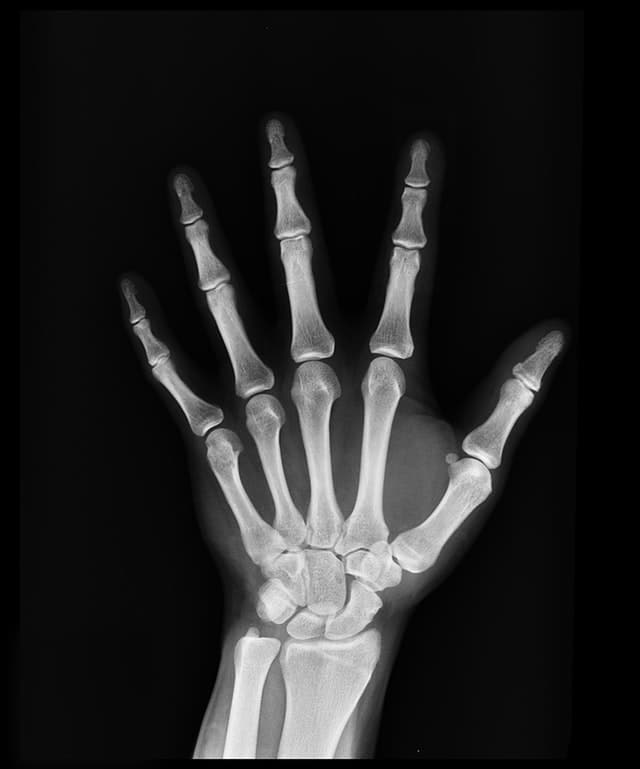

When sound waves enter your ear canal, they strike the eardrum, a thin membrane that is attached to a trio of tiny bones in the middle ear called the ossicles. Osteoporosis causes weakened bones, and when the ossicles are affected, damage to these bones causes hearing loss. The stapes, one of the smallest bones in the human body, is part of the ossicles; its tiny size makes it particularly susceptible to fracture.